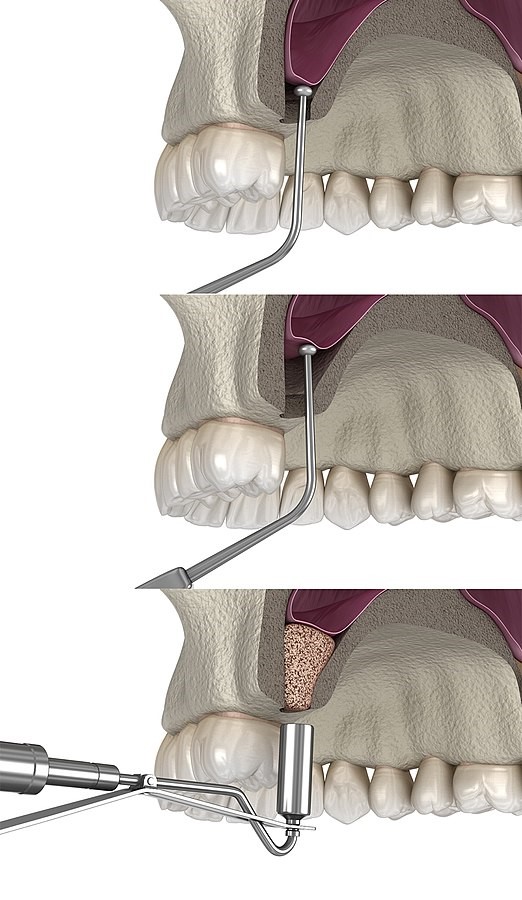

Сложность у операции низкая, и её правильно может сделать практически любой хирург, у которого руки растут из правильного места. С 1964 года всё выполняется часто и довольно рутинно. При синус-лифтинге происходит наращивание костной ткани в области гайморовых пазух, которые расположены в верхней челюсти слева и справа от носа. Когда пациенту удаляют зуб, в месте удаления кость лишается нагрузки. Лишившись нагрузки, кость начинает атрофироваться, и происходит её убыль, из-за чего она начинает приближаться к гайморовой пазухе.

Как выглядит резорбция костной ткани

Вся штука в том, что в гайморовой пазухе отрицательное давление — то есть получается, что с той стороны тоже давит. В конечном итоге из-за этой всесторонней давки становится очень мало кости для того, чтобы поставить имплант. По иронии судьбы там чаще всего располагается самый важный и наиболее подверженный кариесу зуб — шестой жевательный. И именно для того чтобы мы в этом месте смогли поставить пациенту шестой жевательный зуб, гайморову пазуху необходимо приподнять с помощью синус-лифтинга — увеличения объёма костной ткани. Костный трансплантат при этом кладётся в участок, где кровоснабжение идёт с четырёх сторон, поэтому процедура очень надёжна.

Как костный трансплантат увеличивает объём костной ткани